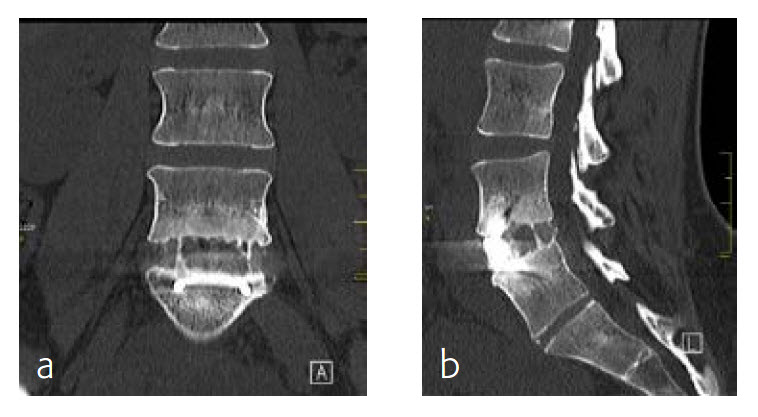

By the planned 6-month follow-up, the patient was pain free and fully active. Evaluation with CT scans was undertaken, consolidation was starting (Fig 8).